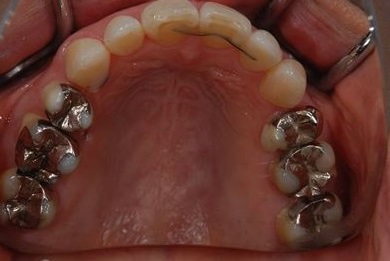

| 治療内容 | インプラント4本(抜歯即日スピードインプラント治療)、ハイブリッドセラミッククラウン6本 | ||||||||||||||||||||||||||||||||